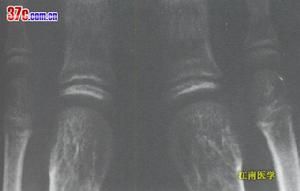

大骨節病 X線表現1、X線表現

⑴ 乾骼型:以乾骼端改變為主,包括臨時鈣化帶變薄、模糊、中斷、消失,乾骼端出現凹陷、硬化等。乾骺型發生於學齡前及學齡兒童,反映骺板軟骨壞死後的繼發變化,代表大骨節病較早的損害,臨床症狀多為陰性或非常輕微。乾骺型的X線變化除很明顯的硬化在非病區兒童中較少見外,其他徵象均可在非病區兒童中出現。因而在同一地區沒有發現Ⅰ度以上典型病例的情況下,不宜僅憑某幾點乾骺端X線改變就診斷為本病。前面談過的日本發現的所謂大骨節病,就是由於沒有充分注意到這一點。